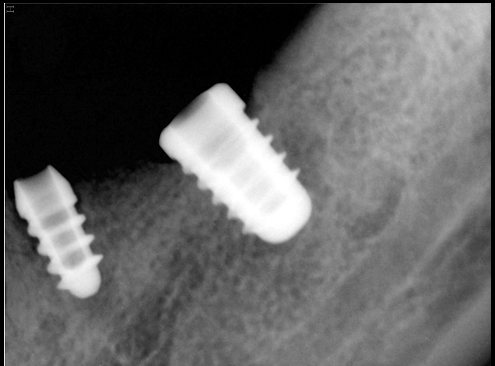

CR/DR 牙齿分割阶段记录

当前进展

- 完成了 CR/DR 牙齿相关分割训练

相关测试

遇到的问题

- 训练过程中出现过 mask 下移问题

- 部分结果会出现 box 填充异常

- mask 边缘仍然有比较明显的锯齿感

参考